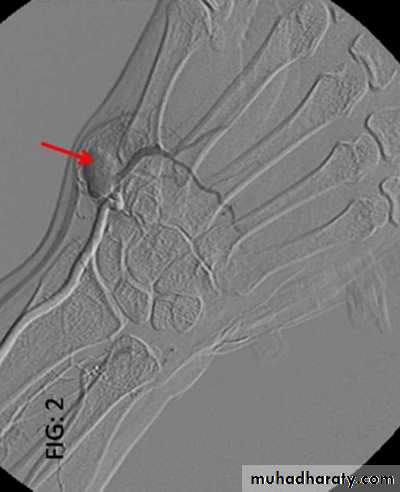

Ulnar artery aneurysm

Angiography show saccular aneurysm of radial artery